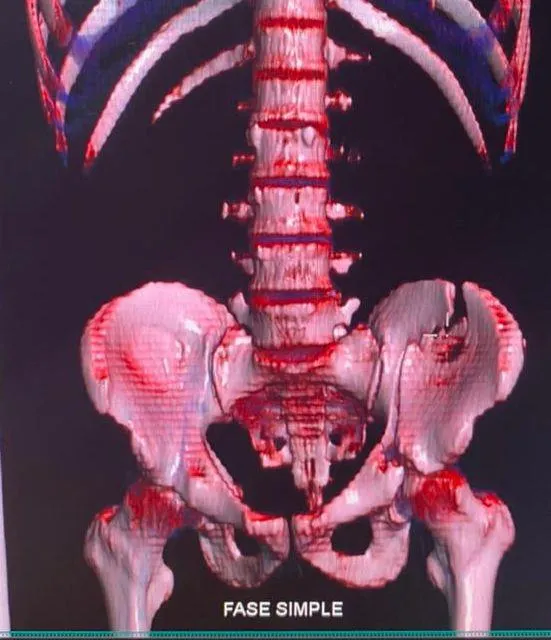

Casos Clínicos

Procedimientos representativos de nuestra práctica en cirugía de cadera, fracturas y prótesis articulares.